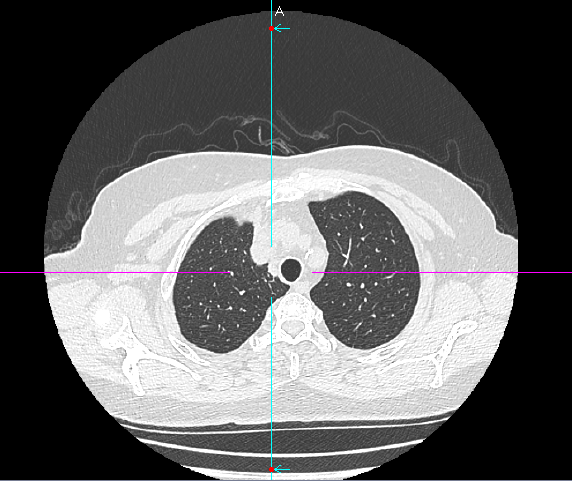

经过团队讨论,一个优化解决方案被提出:启用科室引进的前沿技术——电磁导航支气管镜系统。手术当日,在磁导航的实时引导下,手术团队娴熟地将吲哚菁绿注入目标结节区域,完成了对病灶的精确标定。整个过程患者无任何额外创伤,几乎零出血。

定位完成后,手术进入第二阶段。团队并未在患者胸部留下多个孔洞,而是仅在其肋间开创了一个长约3厘米的单一操作孔。通过这个钥匙孔,高清荧光胸腔镜顺利进入。在之前定位的明确指引下,手术团队迅速而准确地找到了这个深藏不露的结节,精准实施了肺叶部分切除术

术中冰冻病理检查结果表示:(右上肺)结节见实性异型细胞巢,低分化癌首先考虑,结合临床病史,不排除为肺腺癌复发可能。由于患者既往行右中肺叶切除术且本次结节较小考虑复发转移可能,相关病情与家属沟通后确认不再扩大切除,本次手术及时处理、干预精准,明确病理,为患者后续治疗方案提供了指导方针。本次手术尽可能地保住了患者宝贵的健康肺功能。得益于超微创特性与科室成熟的ERAS(加速康复外科)流程,龚女士术后苏醒平稳,疼痛感轻微,术后第二天即可在家属搀扶下下床行走,康复速度远超预期。